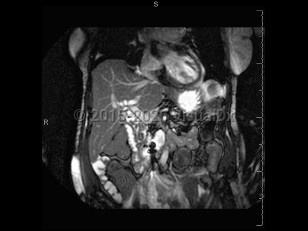

Acute cholangitis is acute inflammation and subsequent infection of the common bile duct. Acute cholangitis typically occurs in the setting of obstruction of the common bile duct. Common etiologies of obstruction include gallstones, strictures (from pancreatitis, biliary procedures, or autoimmune conditions), and malignancy. External compression from the duodenum may also result in obstruction and stasis.

Bile stasis leads to the entry of gastrointestinal bacteria into the normally sterile biliary tree. Gram-negative bacteria, most notably Escherichia coli and Klebsiella pneumoniae, are the most common.